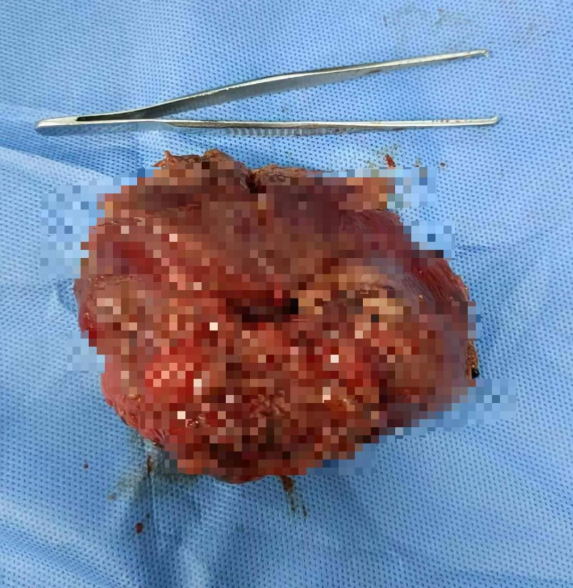

肿瘤标本

手术由杨志坚、黄芳医师双主刀模式执行,麻醉科、手术室密切配合,历时3个多小时,完整切除胆囊及肝脏4b+5段并清扫周围淋巴结。术中荧光引导标记肿瘤切缘,在麻醉科谢广晨医师实施低中心静脉压技术的帮助下,出血不足100ml。在围手术期通过快速康复外科流程,患者术后基本无腹水。病理证实为胆囊低分化腺癌,淋巴结未见转移。术后6天患者顺利出院。